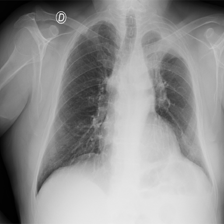

Refer to caption

Figure 1: Distribution of COVID-19. Lesions may be distributed in different locations with different sizes. The corresponding text labels for the images can be categorized into four types: Infection text, Num text, Left Loc text and Right Loc text. STPNet considers different locations and different scales jointly.